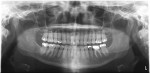

Both CCD and CMOS are solid-state digital technologies that use a one-step process. Sensors for both have multiple electron wells that correspond to picture elements (pixels). The electron wells are covered by a silicon layer. Incoming x-ray photons interact with (ionize) silicon atoms and the freed electrons are collected in the wells. As the electron charge is transferred to a readout photomultiplier (amplifier), it is moved to an analog-to-digital converter. From this electronic data, the software creates the radiolucent and radiopaque areas on the resultant image. The two technologies differ in the pixel readout mechanism, transistor location, and energy requirement. Both types of sensors are ready for reuse once the almost instantaneous readout is completed.5 For digital panoramic radiographs, the pixel array is two pixels wide and uses a scanning movement to acquire the image—similar to a standard photocopier, which actually uses the same technology. The image appears on the computer monitor within seconds of acquisition (Figure 1). Solid-state digital panoramic units are dedicated digital units that do not have analog film capability. Retrofit kits to convert film-based units to solid-state digital are available for some models.